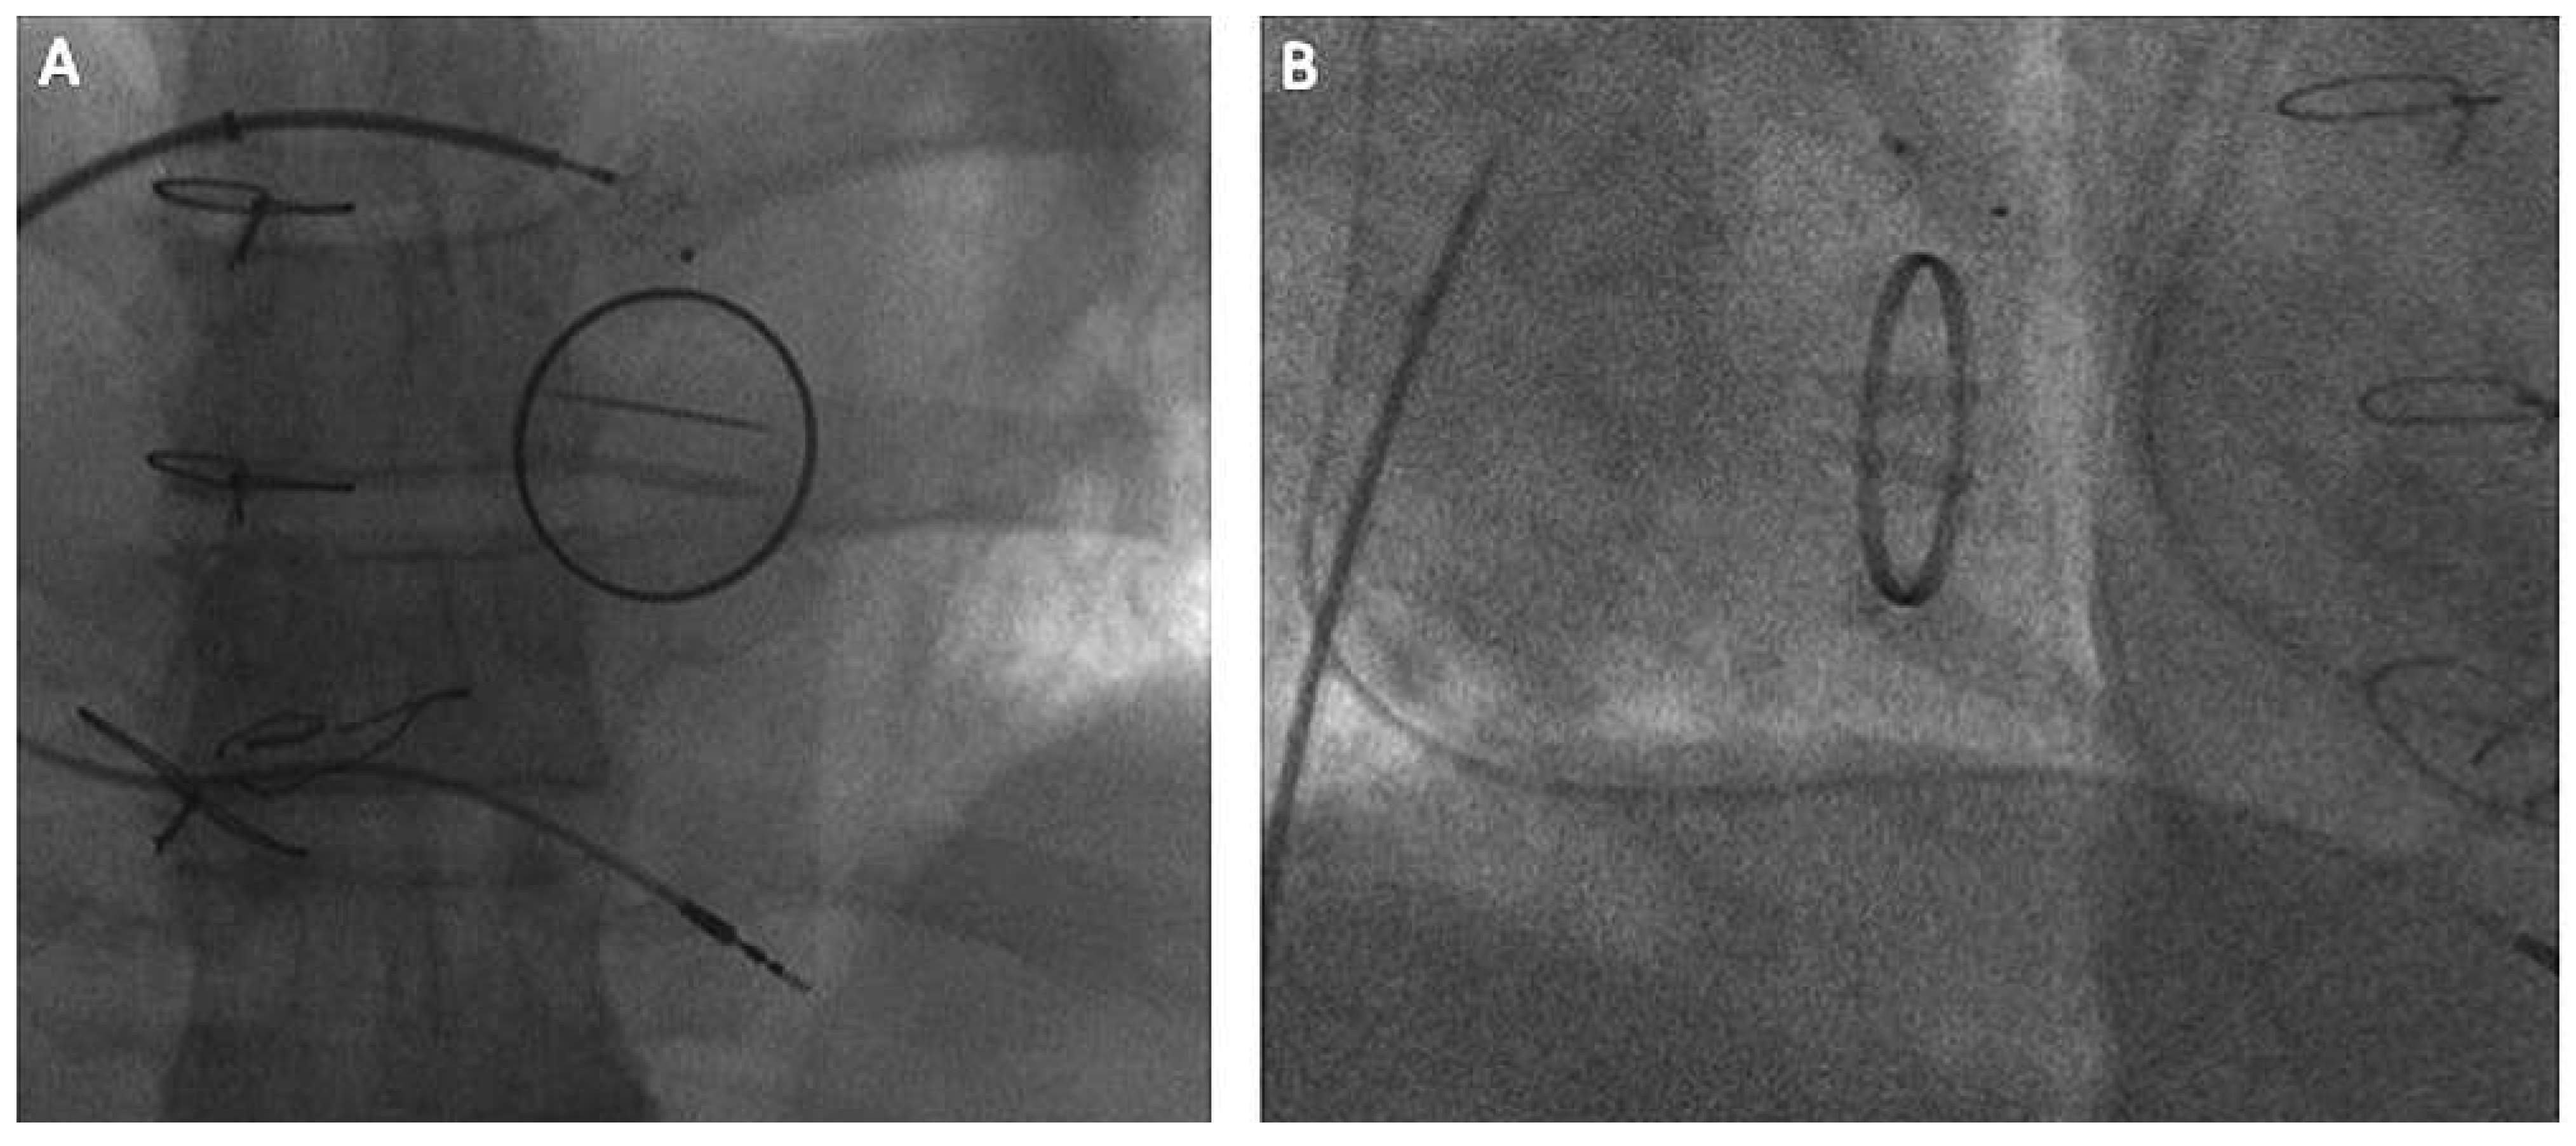

Considerations for aortic paravalvular leak

Alternative approach